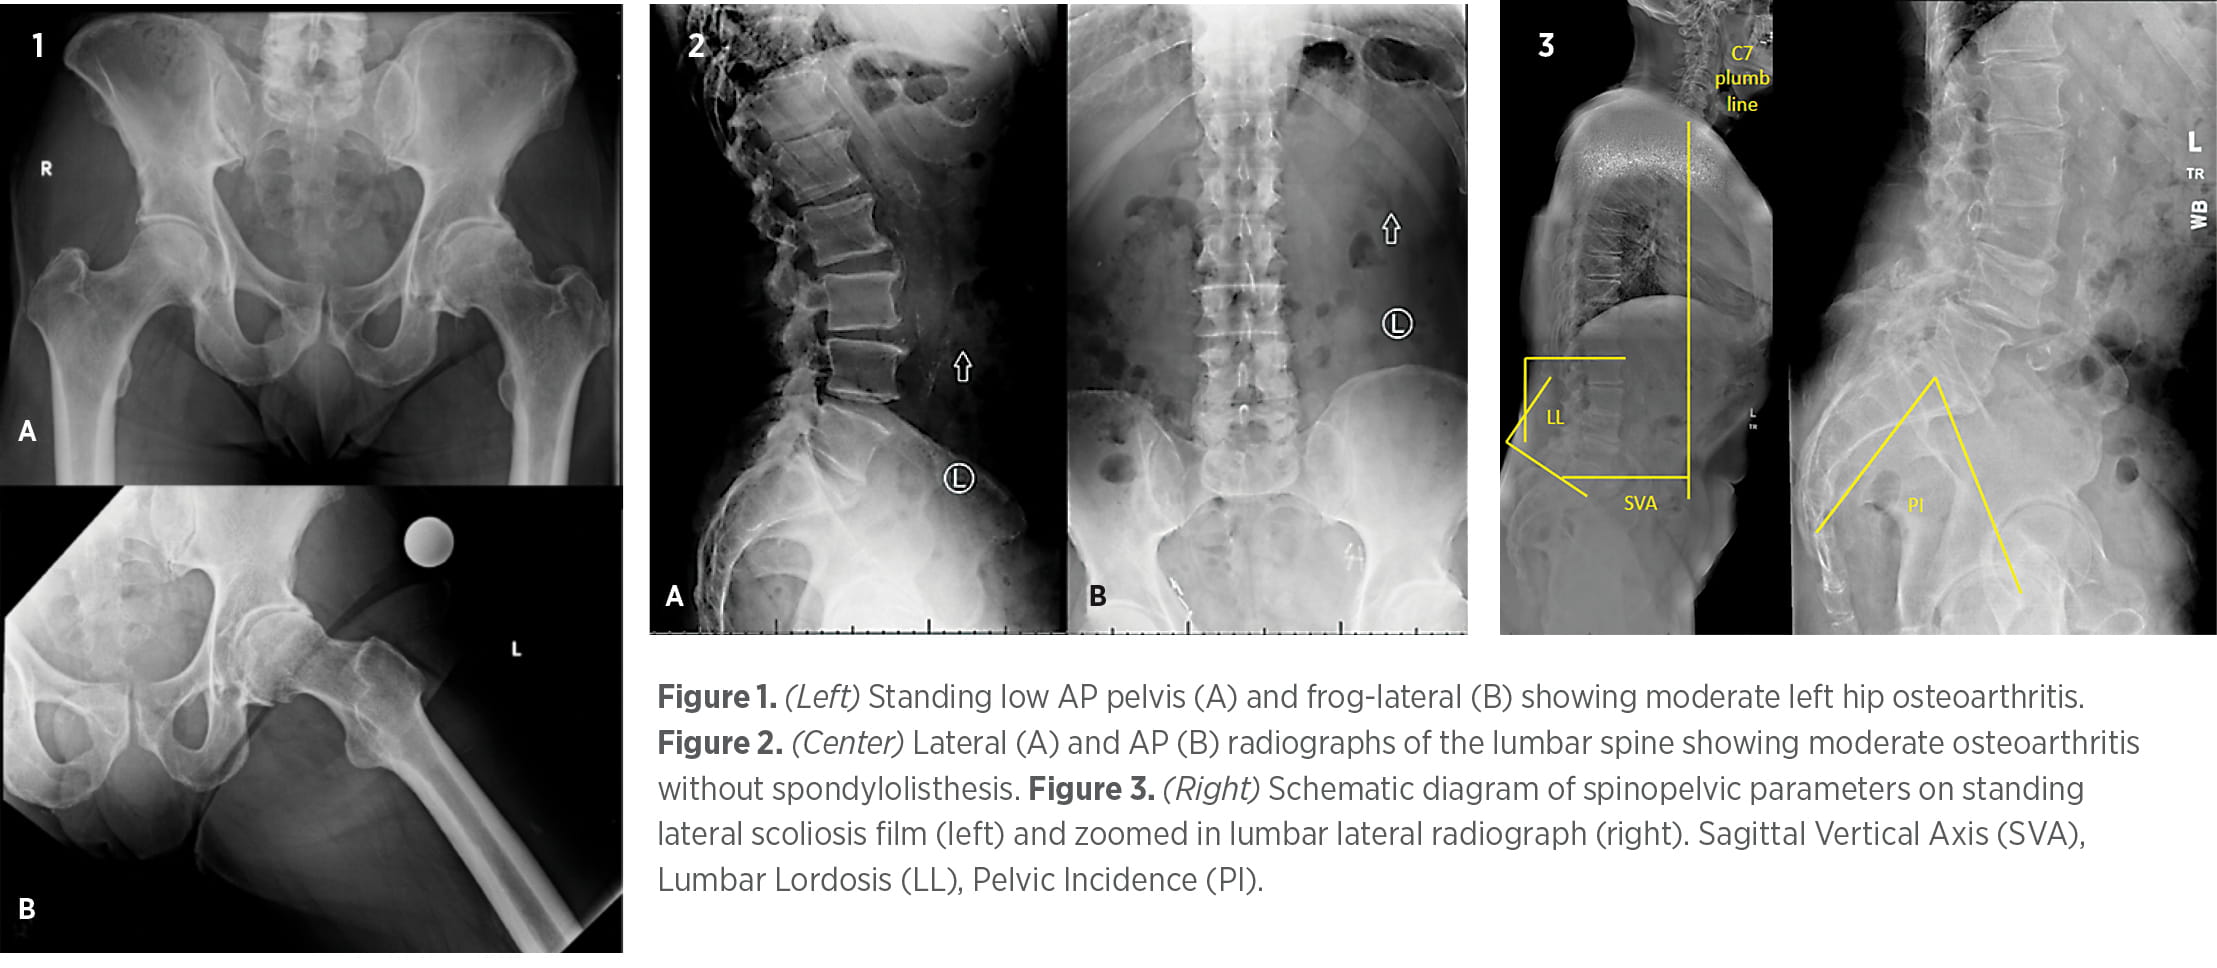

Standard standing AP pelvis, cross-table lateral, and frog-leg radiographs can be used to evaluate the hip joint (e.g., Figure 1). CTs and AP radiographs can be used to assess alignment and positioning of either the native hip or arthroplasty components, including acetabular anteversion and inclination, femoral version and inclination, femoral offset, and leg-length discrepancy. Pain relief upon fluoroscopically guided hip injection in patients with radiographic OA suggests primary hip pathology, and incomplete or no pain relief suggests a lumbar pathology.1 Pain relief upon intra-articular bupivacaine injection was found to be 87% sensitive and 100% specific to a primary hip pathology.13

AP and lateral flexion-extension radiographs are first-line tests for suspected lumbar pathologies, and full-length lateral standing radiographs should be obtained to determine spinal curvature and spinopelvic sagittal balance (Figures 2 and 3). Lumbar spine MRIs are used to assess soft tissue and bony impingements, including nerve root and cord compression (Figure 4). Pain relief with an epidural steroid injection (ESI) suggests a primary spinal pathology. However, patients for whom ESIs have not provided pain relief may improve following lumbar decompression,12 so a negative response to ESI should not exclude the lumbar spine as the underlying cause of symptoms.

Figures 1, 2, and 4 represent clinical radiographs from the same patient. Their clinical presentation is left-sided low back, buttock, hip, and groin pain without clear radicular pathology. So, is it the hip or the spine, or both?